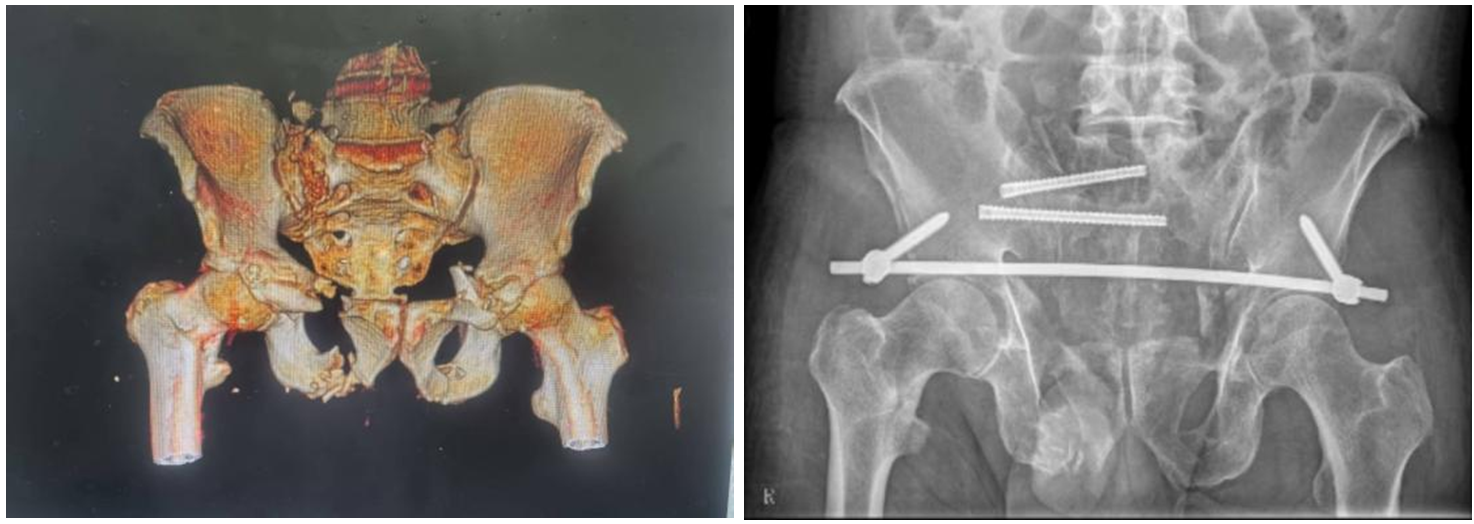

术前CT检查及术后X线检查。(翻拍图片)

术中在机器人的导航下顺利植入骶髂螺钉。